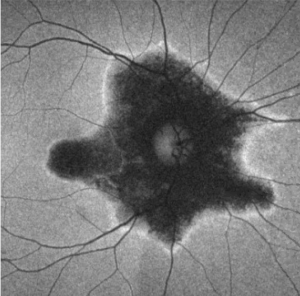

Fundus Autofluorescence (FAF)

FAF is extremely useful in defining the areas of retinal involvement and monitor for signs of progression.[15][16] FAF documents the presence and distribution of lipofuscin in the RPE cells; a decrease in autofluorescence indicates loss or damage to the RPE cells with hyperautofluorescence indicating increased metabolic activity.[16]

Mrejen et al describe a trizonal defect appearance on FAF, correlating to the similar trizonal pattern observed on OCT. Normal autofluorescence can be observed in the area outside of the delineating line (zone 1), speckled hyperautofluorescence could be seen within the AZOOR lesion (zone 2), and hypoautofluorescence was present indicating RPE/choroidal atrophy (zone 3).[13]